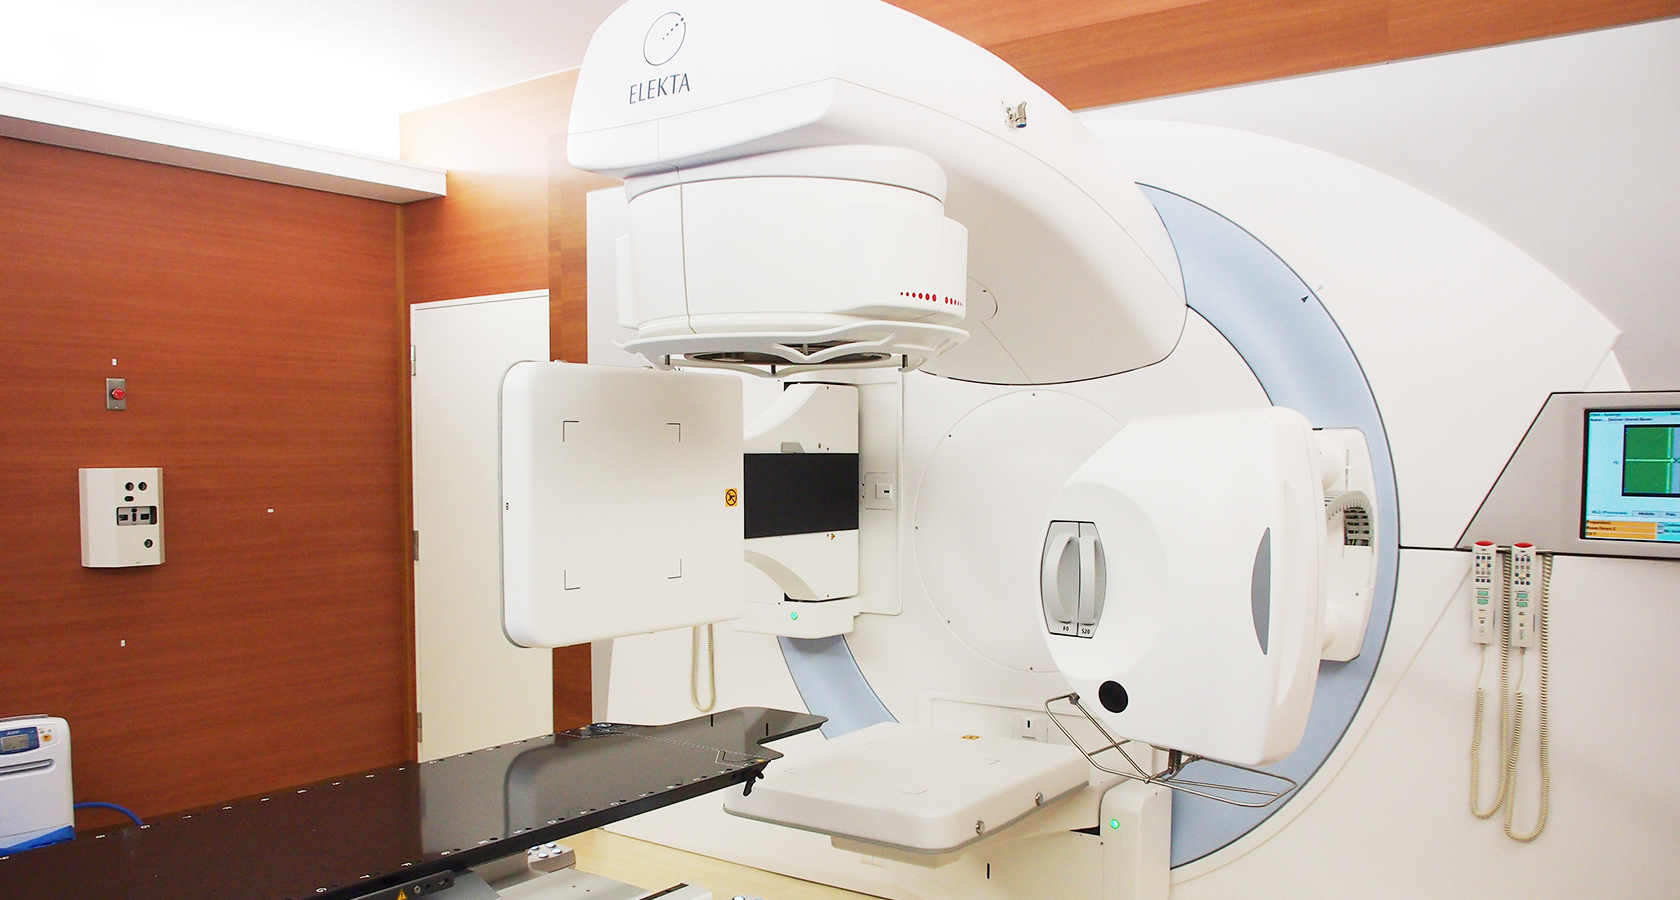

新治療装置での治療例を紹介します。いずれも治療は1回3分程度で完了します。